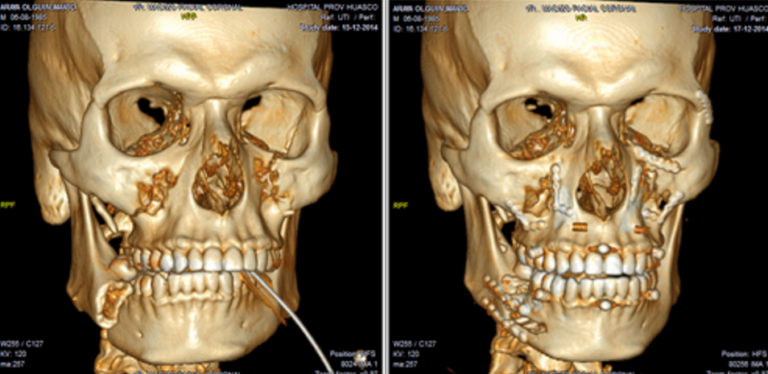

Implantes cigomáticos y rehabilitación dental

Los implantes cigomáticos son una opción para la rehabilitación dental de pacientes con pérdida ósea...